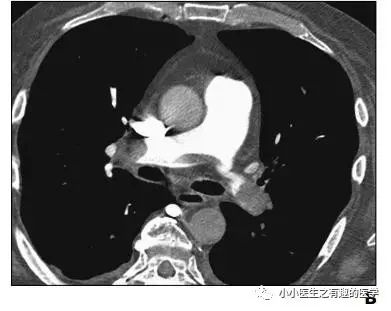

其实,我大中华也有医生用CT平扫发现可疑肺栓塞。

下面是上海交通大学的论文

3.吴世明, 陈龙兴, 唐震. CT平扫在急性肺栓塞中的诊断意义[J]. 医学影像学杂志, 2017, 27(4):652-655.